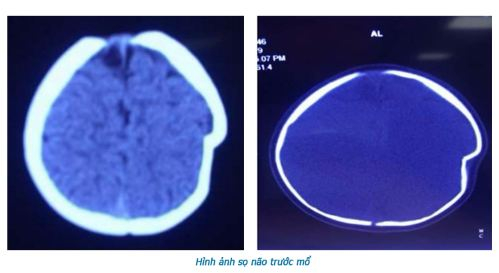

Thông qua các tiện ích của bệnh án điện tử, việc điều trị cho người bệnh luôn được công khai, minh bạch, rõ ràng, tránh sai sót đáng tiếc xảy ra. trên cơ sở triển khai thí điểm PACS, đã giúp truy xuất nhanh chóng và lưu trữ hình ảnh dữ liệu một cách kinh tế nhất. Bác sĩ xem được hình ảnh y khoa bất kỳ nơi nào, tiết kiệm thời gian, nâng cao chất lượng chẩn đoán, điều trị, giúp cho việc nghiên cứu khoa học, hội chẩn, đào tạo từ xa ở trong nước và nước ngoài được phát triển.

Trước đó, từ năm 2016, BVĐK tỉnh Phú Thọ đã thực hiện triển khai hệ thống phần mềm PASC trong chẩn đoán hình ảnh và đến tháng 7/2017, bệnh viện chính thức sử dụng hệ thống PASC Thời gian phục vụ người bệnh được rút ngắn đáng kể, đặc biệt là đối với chụp CT, MRI do không phải lựa chọn ảnh để in phim và không tốn thời gian cho in phim. Đặc biệt, tiết kiệm, giảm chi phí liên quan đến sử dụng phim X.quang; giảm bớt đáng kể lượng vật tư tiêu hao như: hóa chất, túi đựng phim, phim các loại…